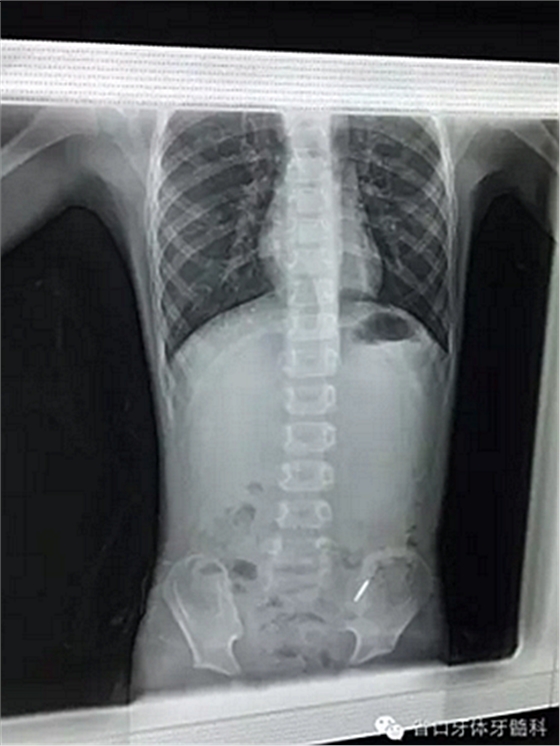

2) 異物被誤吞后的應(yīng)對:如果發(fā)現(xiàn)患者將異物誤吞,當事醫(yī)生或科室負責(zé)人應(yīng)立即將事件詳情告知患者及家屬,安撫患者及家屬情緒。護士應(yīng)密切觀察患者的生命體征,留意患者是否有嗆咳或其它異常反應(yīng)。立即讓患者平躺,取頭低腳高位或墊高腰臀部,以免異物落入更深部位,放射科拍攝胸腹平片,確定異物位置,根據(jù)異物在體內(nèi)滯留位置,制定下一步處理方案。

3) 異物誤咽入消化道的應(yīng)對(見附圖1- 2): 口腔異物誤咽入消化道后,患者可以無任何癥狀,但異物可能在其解剖狹窄部位嵌頓,如食道的3 個生理狹窄、胃幽門部與回盲部。食道的3個生理狹窄分別位于:食道的起始部、食道與氣管交叉處、食道與膈肌交界處。食道的第二個狹窄處由于鄰近氣管、支氣管、肺動靜脈及主動脈,若異物(尤其是尖銳或邊緣銳利的異物)嵌頓此處,不及時取出,極有可能導(dǎo)致食道縱隔瘺、食道氣管瘺、食道肺動脈瘺及食道主動脈瘺等嚴重并發(fā)癥而危及患者的生命安全[15]。入胃異物的尖銳處也可能會勾傷消化道壁, 引起消化道梗阻、穿孔, 繼發(fā)出血與感染[10]。

附圖1 誤吞入消化道的G鉆

Figue 1 G drill in gastrointestinal tract

附圖2 自然排出的G鉆

Figue 2 G drill passed naturally out of body